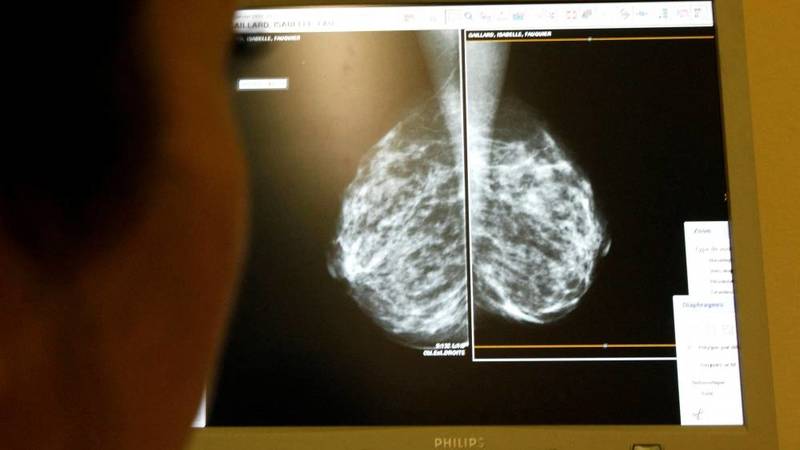

أوصت هيئة استشارية أمريكية للصحة العامة الثلاثاء، النساء بالبدء في تصوير الثدي بالأشعة السينية في سن الأربعين وليس الخمسين وفق التوصيات السابقة، في تغيير يقول الخبراء إنه يمكن أن ينقذ آلاف الأرواح.

ودعت فرقة العمل الأمريكية المعنية بالخدمات الوقائية -والتي يتم اتباع توصياتها على نطاق واسع- النساء اعتباراً من سن الأربعين إلى إجراء هذا الفحص الذي يهدف إلى الكشف عن سرطان الثدي كل عامين.

وبحسب هذه الهيئة، من شأن خفض العمر إلى 40 عاماً إنقاذ مزيد من الأرواح بنسبة 19% مقارنة بتلك التي يتم إنقاذها مع اعتماد الخمسين كسنّ دنيا لهذه الصور الشعاعية.